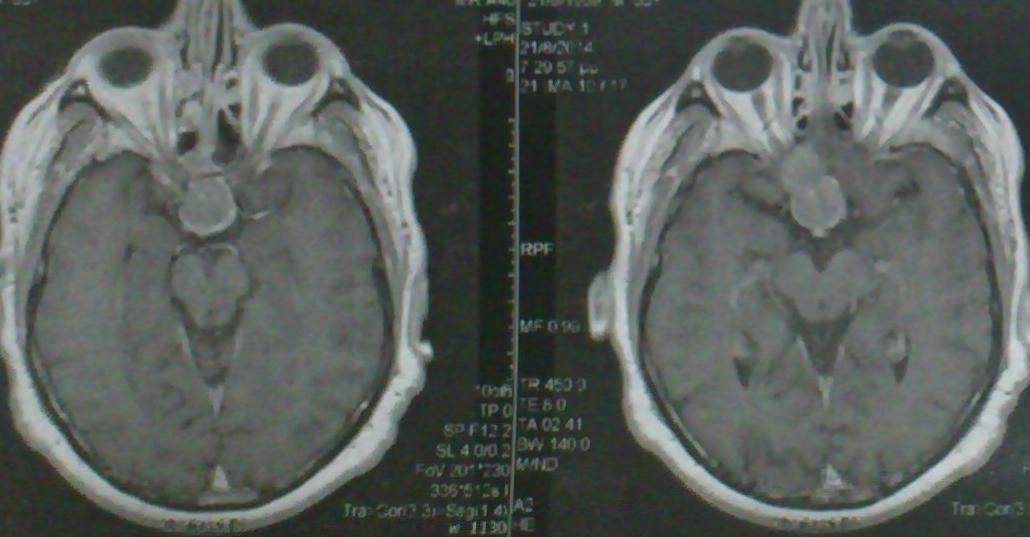

Ασθενής   55 ετών  ο οποίος είχε υποβληθεί  προ 3μήνου σε ενδοσκοπική διασφηνοειδική αφαίρεση μακροαδενώματος υπόφυσης  ( αδύνατη λόγω σκληρής σύστασης του όγκου η αφαίρεση του υπερεφιππιακού τμήματος του όγκου) προσήλθε στην κλινική μας  με σκοπό την αφαίρεση  του υπερεφιππιακού τμήματος του όγκου  δια υπερόφρυας τομής δέρματος και δεξιάς mini orbitozygomatic keyhole approach.  Η μετεγχειρητική του πορεία ήταν ομαλή με περαιτέρω βελτίωση των οπτικών του πεδίων ( αρχική μικρή  βελτίωση μετά την ενδοσκοπική διασφηνοειδική προσπέλαση ) και ο απεικονιστικός έλεγχος ανέδειξε την πλήρη αφαίρεση του υπολειμματικού όγκου.

Προεγχειρητικός απεικονιστικός έλεγχος